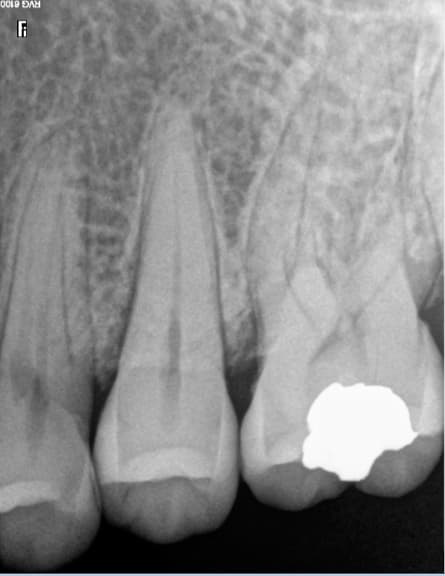

Moi capteur rvg, ca me suffit largement. La manipulation des plaques est éliminatoire pour moi.

Pas suffisamment fin pour détecter cette fêlure sur cette 26 qui sera à extraire ( infection, pas de vitalité) mais une radio argentique n'aurait pas fait mieux. -)